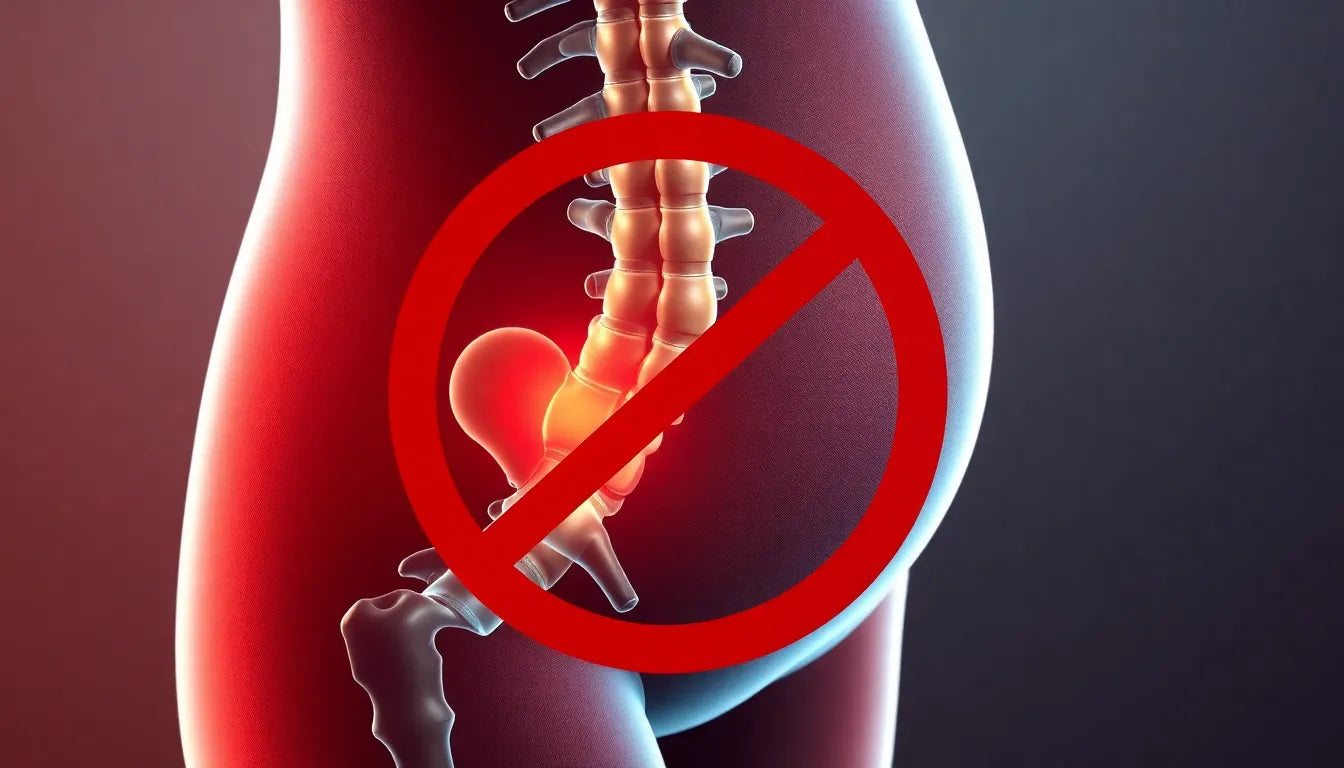

Leven zonder pijn: hoe een hernie discale je jambe beïnvloedt en wat je kunt doen

Een hernie discale, of hernia, kan zenuwen in de wervelkolom comprimeren, wat leidt tot pijn, gevoelloosheid en in ernstige gevallen verlamming van de jambe. Vroege diagnose en behandeling zijn cru...